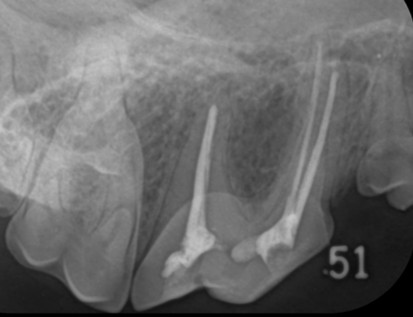

2.根管充填

歯に歯根に通じる穴をあけます。その穴から歯髄を抜いて(抜髄)、根管を拡大・形成します。洗浄・乾燥させて後、拡大した根管に、詰め物をしていきます

処置後は、定期的に処置をした歯のレントゲン検査を行い、細菌感染などがないか経過観察していきます